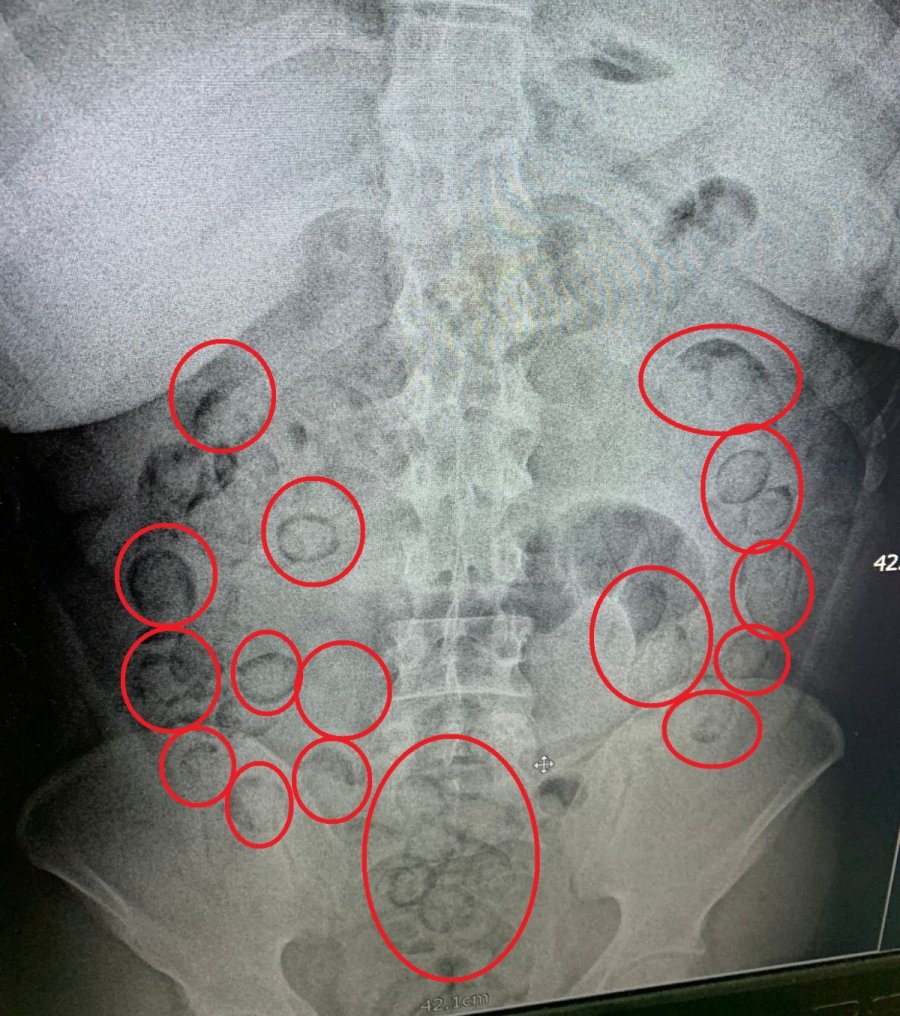

Aksaray'da narkotik ekiplerince düzenlenen operasyonda yakalanan İran uyruklu uyuşturucu tacirinin midesinde 101 parça halinde 433 gram metamfetamin maddesi ele geçirildi.

Edinilen bilgiye göre, İl Emniyet Müdürlüğü Narkotik Suçlarla Mücadele Şubesi ekipleri, yaptığı analiz çalışmasında İran'ın başkenti Tahran'dan ülkeye uyuşturucu getirileceği bilgisine ulaştı. Bunun üzerine Aksaray Cumhuriyet Başsavcılığı koordinesinde harekete geçen ekipler kimliği belirlenen A.M. (20) isimli İran uyruklu şahsı teknik ve fiziki takibe aldı. Narkotik ekipleri şahsın uçakla Ankara'ya geleceği bilgisi üzerine harekete geçti. Ekipler Ankara'da uçaktan inen şahsı takibe aldı. Ankara'dan otobüse binen uyuşturucu taciri otobüsle Aksaray'a geldi. Aksaray'da E-90 karayolunda şahsın otobüsten inmesi üzerine operasyon için düğmeye basan ekipler şahsı kıskıvrak yakalayarak gözaltına aldı. Yapılan kontrollerin ardından uyuşturucuları midesine yutarak muhafaza ettiği düşünülen şahıs Aksaray Eğitim ve Araştırma Hastanesine götürülerek iç beden muayenesinden geçirildi. Tomografisi çekilen şahsın midesinde vücut dışı parçaların olduğu tespit edildi. Hastanede doktor kontrolünde ilaç içirilen İran uyruklu tacir bir süre sonra polis kontrolünde büyük tuvaletini yaparken, şahsın midesinden prezervatife sarılmış 101 küçük paket çıktı. Paketlerin içini açan polis, toplam 433 gram metamfetamin maddesi ele geçirdi. Uyuşturucu maddelere el konulurken, uyuşturucu taciri emniyetteki işlemlerinin ardından sevk edildiği adli makamlarca tutuklanarak cezaevine gönderildi.